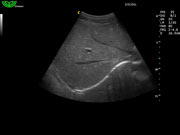

Алгоритм снижения зернистости изображения (SPA)

- Программный расчет в реальном времени.

- Позволяет различать малейшие различия в тканях.

- Удаляет шум и делает нечеткие края более различимыми.

- Удаляет шум и делает изображение более похожим на анатомические стандарты.